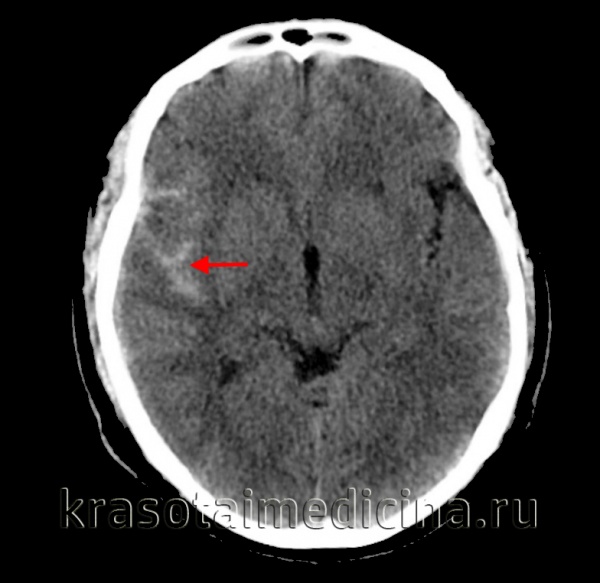

Распространение крови при травматическом САК:

- Обычно сочетается с другими признаками ТЧМТ (отек, очаги ушиба, эпидуральные, субдуральные гематомы)

- Кровь расположена более поверхостно вокруг корковых структур

КТ является первоначальным исследованием, при помощи которого обязательно определить степень согласно шкалы Фишер (Fischer). Диагноз САК подозревается при наличии уплотнения субарахноидальных пространств.

Чувствительность метода снижается с течением времени (100% в течение первых 12 часов, 93% в течение 24 часов, 50% в течение 7 дней).Распространение крови на при аневризматическом САК